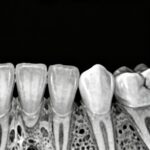

With over 15 years of experience at the intersection of dental and medical imaging — including a one year internship at East Orange Carewell Health Hospital in New Jersey focused on ultrasound, MRI, and medical CT — my passion for radiology has grown into lifelong commitment. I founded OralRad360 to offer dentists precise and insightful CBCT interpretation reports, helping them achieve accurate diagnoses, confident treatment planning, and ultimately, better patient outcomes.

Having personally interpreted more than 6000 Cone Beam CT (CBCT) scans, I understand the critical importance of accuracy, clarity, and clinical relevance in every radiologic report.

- CBCT interpretation, Rule out pathology, Implant planning, TMJs, Sinuses, Endodontics, Orthodontics, Airway Analysis.